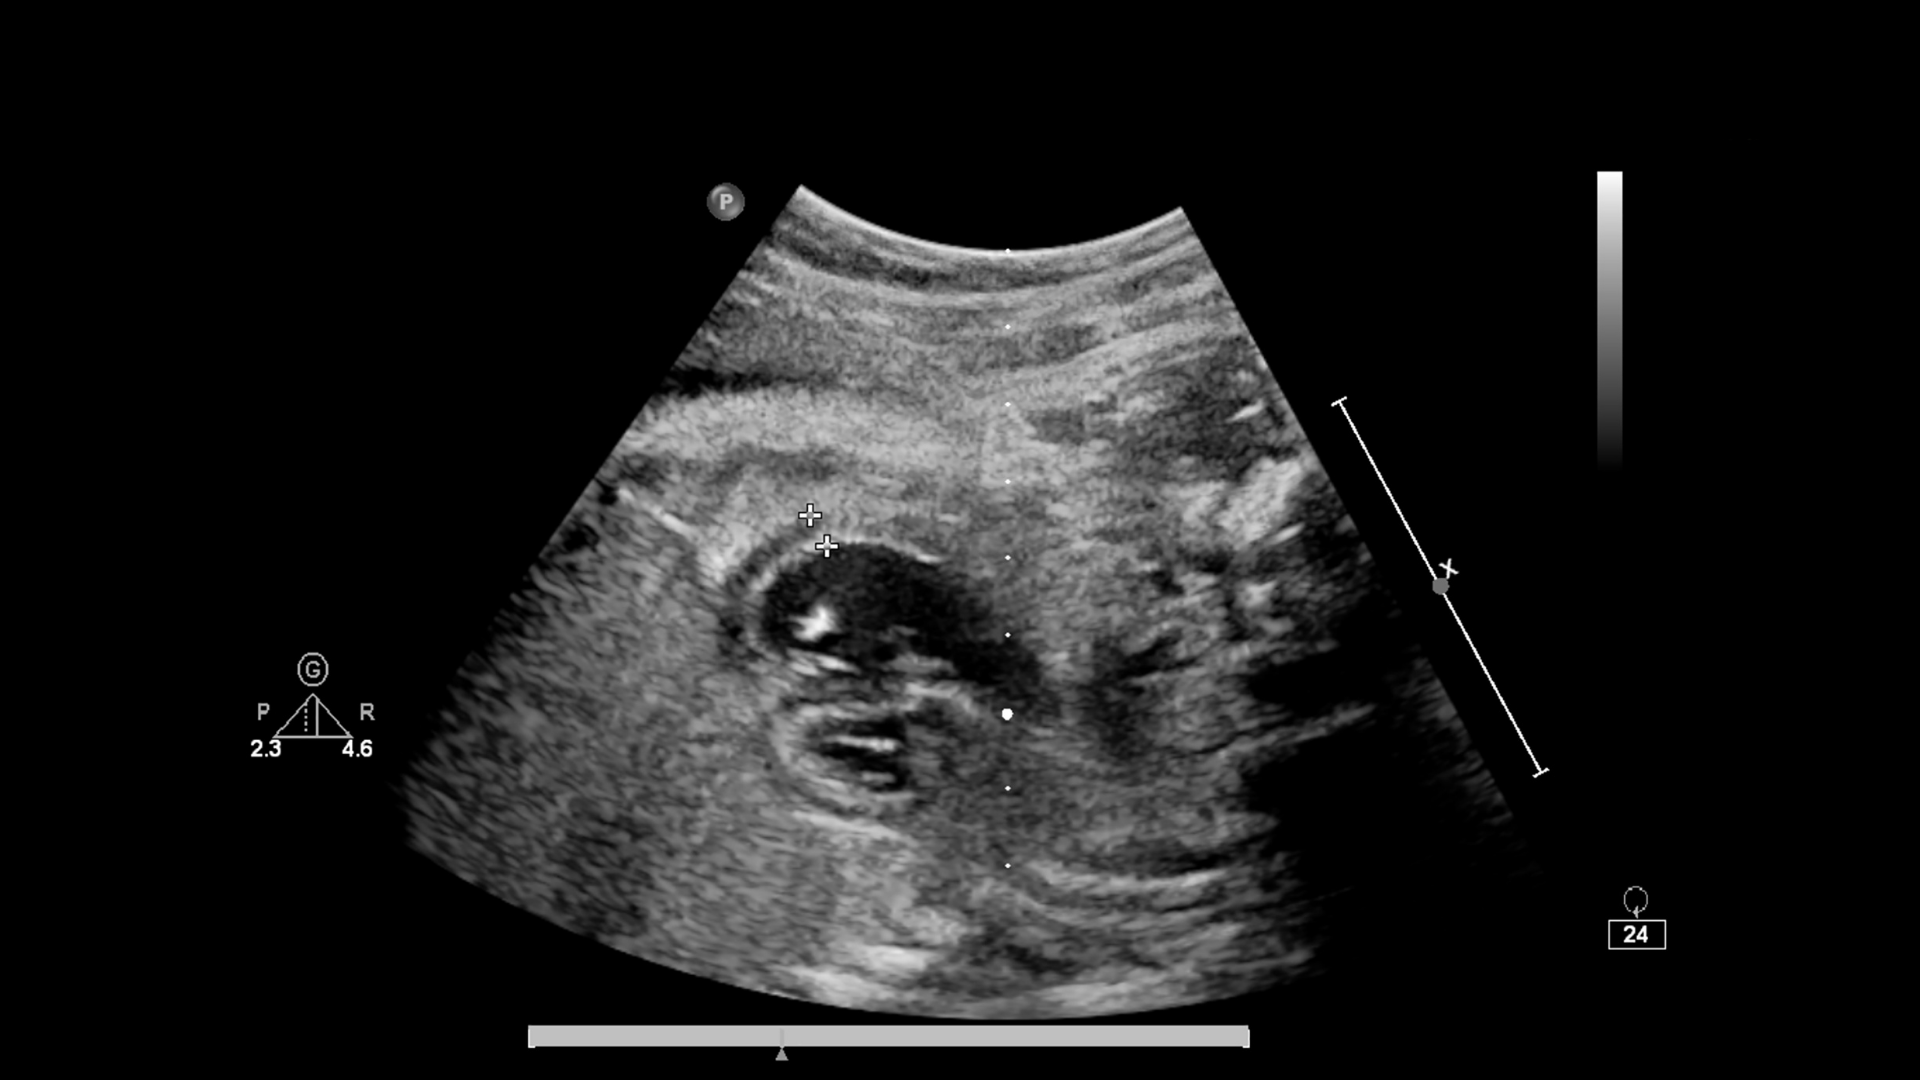

Vôi hoá gan là hiện tượng các muối canxi lắng đọng trong mô gan hoặc trong những tổn thương đã tồn tại từ trước. Trên các phương pháp chẩn đoán hình ảnh như siêu âm, CT hoặc X-quang, những vùng này thường biểu hiện dưới dạng điểm hoặc mảng sáng trong nhu mô gan.

- Siêu âm gan.

Các kỹ thuật này giúp xác định vị trí, kích thước và đặc điểm của nốt vôi hóa.